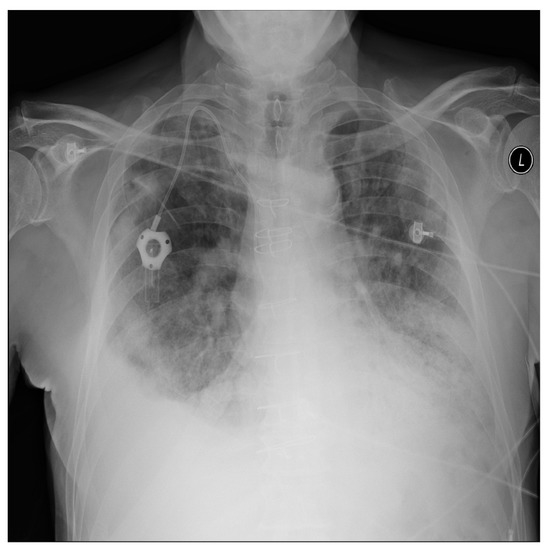

For a more intuitive understanding, we visualize a sample of each category in Figure 9, Figure 10 and Figure 11.

Figure 10. Pneumonia sample: X-ray Image dataset.

Applsci 13 00454 g010